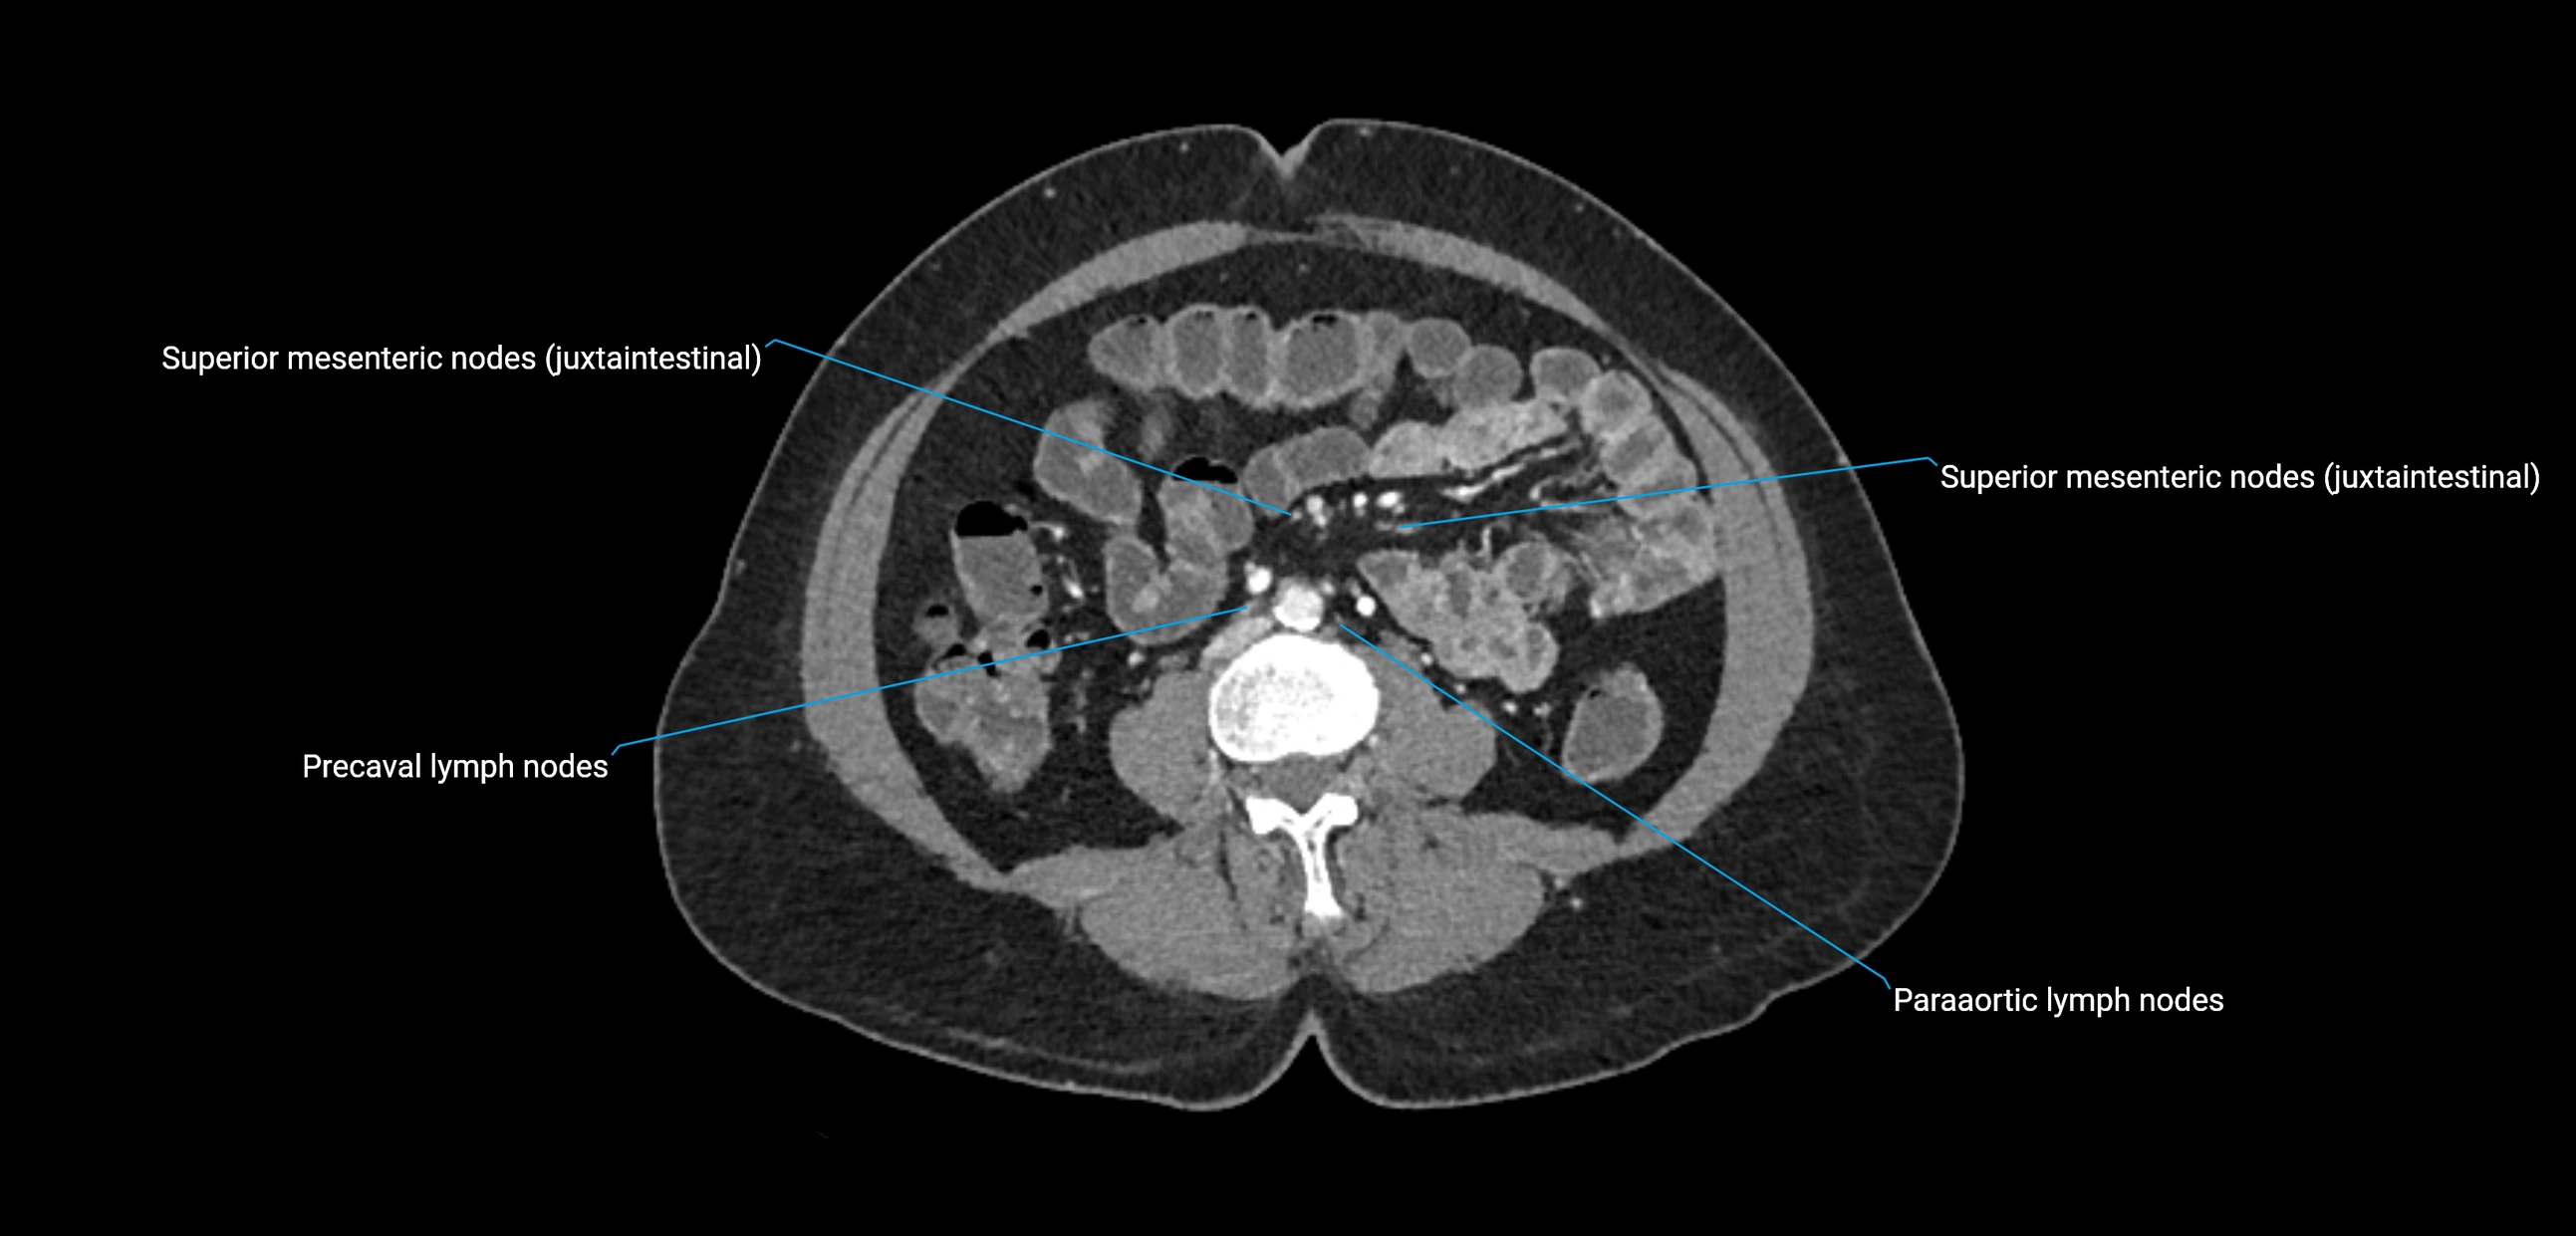

The lateral aortic lymph nodes (also called para-aortic lymph nodes) are a major group of retroperitoneal lymph nodes located along the abdominal aorta and its branches. They lie between the diaphragmatic crura superiorly and the bifurcation of the aorta at L4 inferiorly.

They are positioned on both sides of the abdominal aorta:

• Right lateral aortic nodes: adjacent to the inferior vena cava (IVC)

• Left lateral aortic nodes: lateral to the abdominal aorta

CT image

image